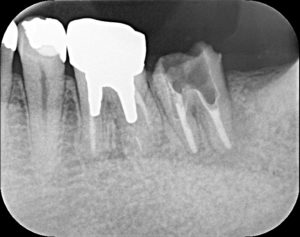

当院の取り組みとして、高倍率の拡大鏡を使用することで、裸眼と比較するとかなり細部まで確認することができます。その結果が、こちらのレントゲン写真。

【術前】

画面向かって一番右の歯です。

今回の治療で困難なことは下記の2点。

①かなり太い土台が入っているため、除去する際、歯に穴があいてしまう可能性がある。そうすると、抜歯  に至るケースもある。

②根の中の虫歯を可能な限り除去する必要がある。

①に関しては高倍率の拡大鏡の使用

②に関しては、特殊な器具(ニッケルチタンやダイヤモンドの超音波チップ)の使用や薬品の使用

上記に記載した方法で対応しました。